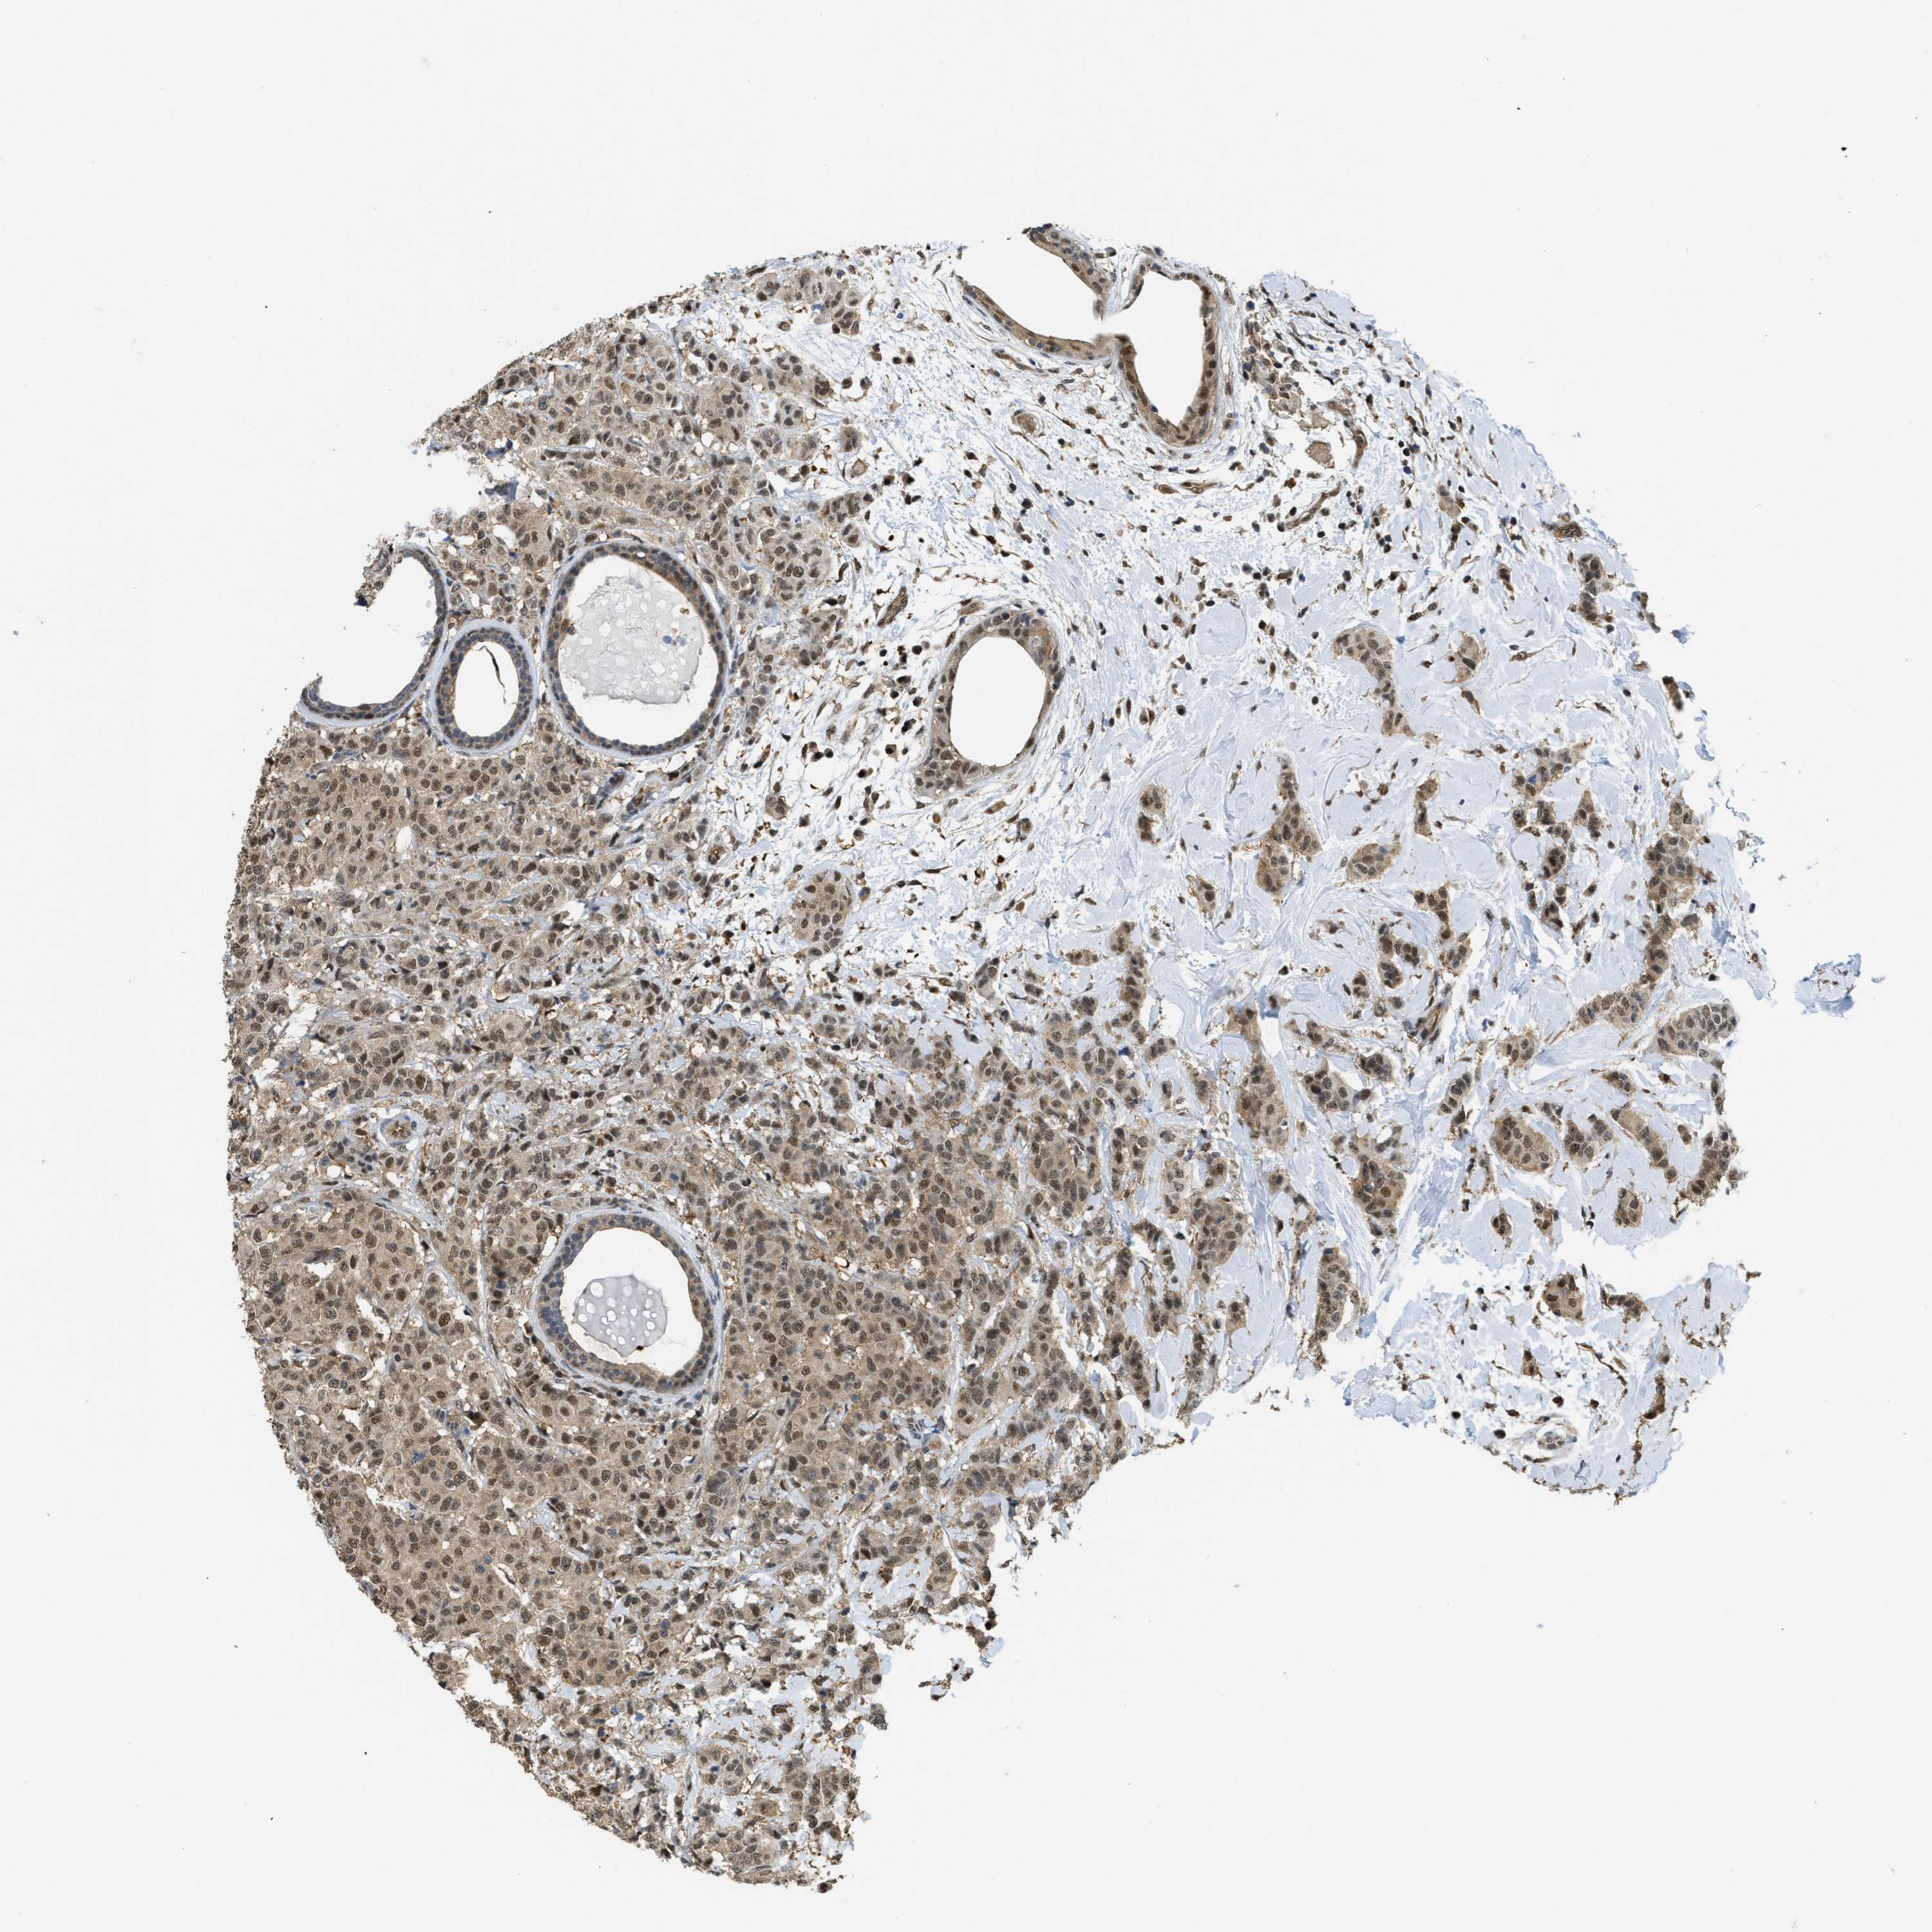

CANCER BREAST CANCER Show tissue menu

Breast cancer

Human cancer